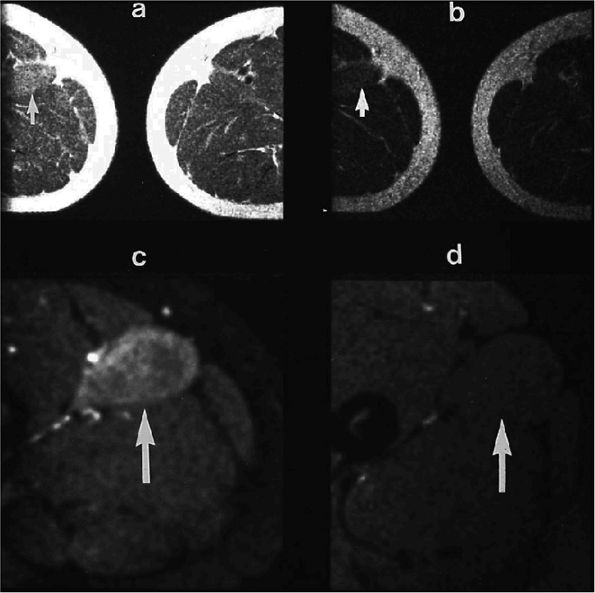

FIGURE 3.49 ● A normal cortical articular ridge of the acetabulum (arrow) is seen on (A) T2*-weighted coronal and (B) 3D CT images. This bony ridge should not be mistaken for osseous pathology. The acetabular notch (open arrow) is shown on the 3D CT rendering. (A: TR, 400 msec; TE, 20 msec; flip angle, 25°). (C) Arthroscopic view of acetabular notch.